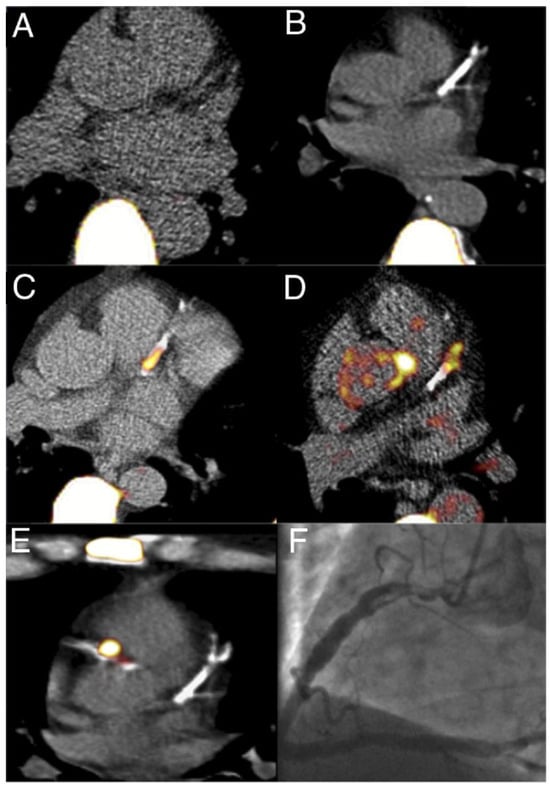

- Joshi, N.V.; Vesey, A.T.; Williams, M.C.; Shah, A.S.V.; A Calvert, P.; Craighead, F.H.M.; Yeoh, S.E.; Wallace, W.; Salter, D.; Fletcher, A.M.; et al. 18F-fluoride positron emission tomography for identification of ruptured and high-risk coronary atherosclerotic plaques: A prospective clinical trial. Lancet 2014, 383, 705–713. [Google Scholar] [CrossRef]

- Lee, J.M.; Bang, J.-I.; Koo, B.-K.; Hwang, D.; Park, J.; Zhang, J.; Yaliang, T.; Suh, M.; Paeng, J.C.; Shiono, Y.; et al. Clinical Relevance of 18 F-Sodium Fluoride Positron-Emission Tomography in Noninvasive Identification of High-Risk Plaque in Patients With Coronary Artery Disease. Circ. Cardiovasc. Imaging. 2017, 10. [Google Scholar] [CrossRef]

| 37 | Prospective | 18F NaF TBRmax is higher (1.66) in culprit lesions than non-culprit lesions (1.24; p < 0.0001). By comparison, 18F FDG showed a ratio of 1.71 and 1.58 (p = 0.34) for culprit and non-culprit lesions, respectively. IVUS with features of high-risk plaques had a mean 18F NaF ratio of 1.90. | [28] |

| 51 | Prospective | 18F NaF positive lesions had high plaque burden than IVUS and OCT. 14/15 IVUS and OCT identified high-risk lesions had high 18F NaF uptake. | [30] |